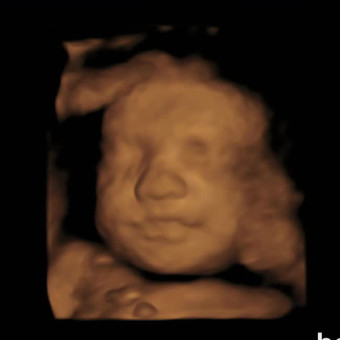

Baby De Jager Registry

Reece & Nathan De Jager

We are so grateful for your love and support as we prepare to welcome our baby boy. Thank you for thinking of our little one!